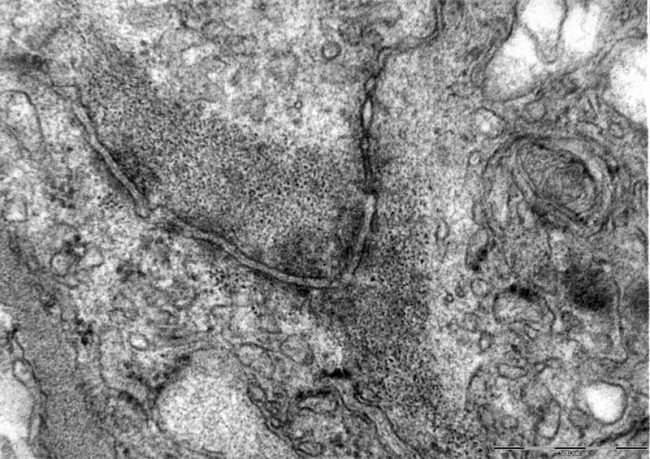

- Electron Microscope

- Electron Microscope